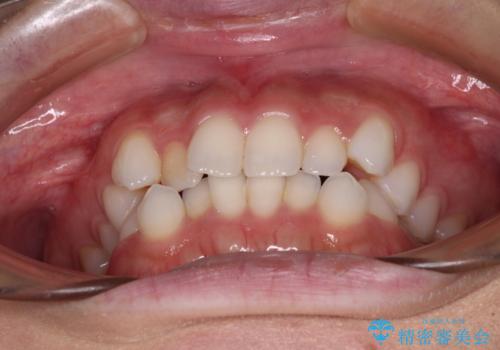

前歯のデコボコとクロスバイト ワイヤー装置での抜歯矯正

- 前歯のデコボコとクロスバイトを気にして来院された患者様です。

上下ともにデコボコはそれほど強くありませんでしたが、非抜歯では口元が突出した仕上がりとなる可能性があるため、上下左右の第一小臼歯4本を抜歯し、ワイヤー装置での抜歯矯正を行うこととしました